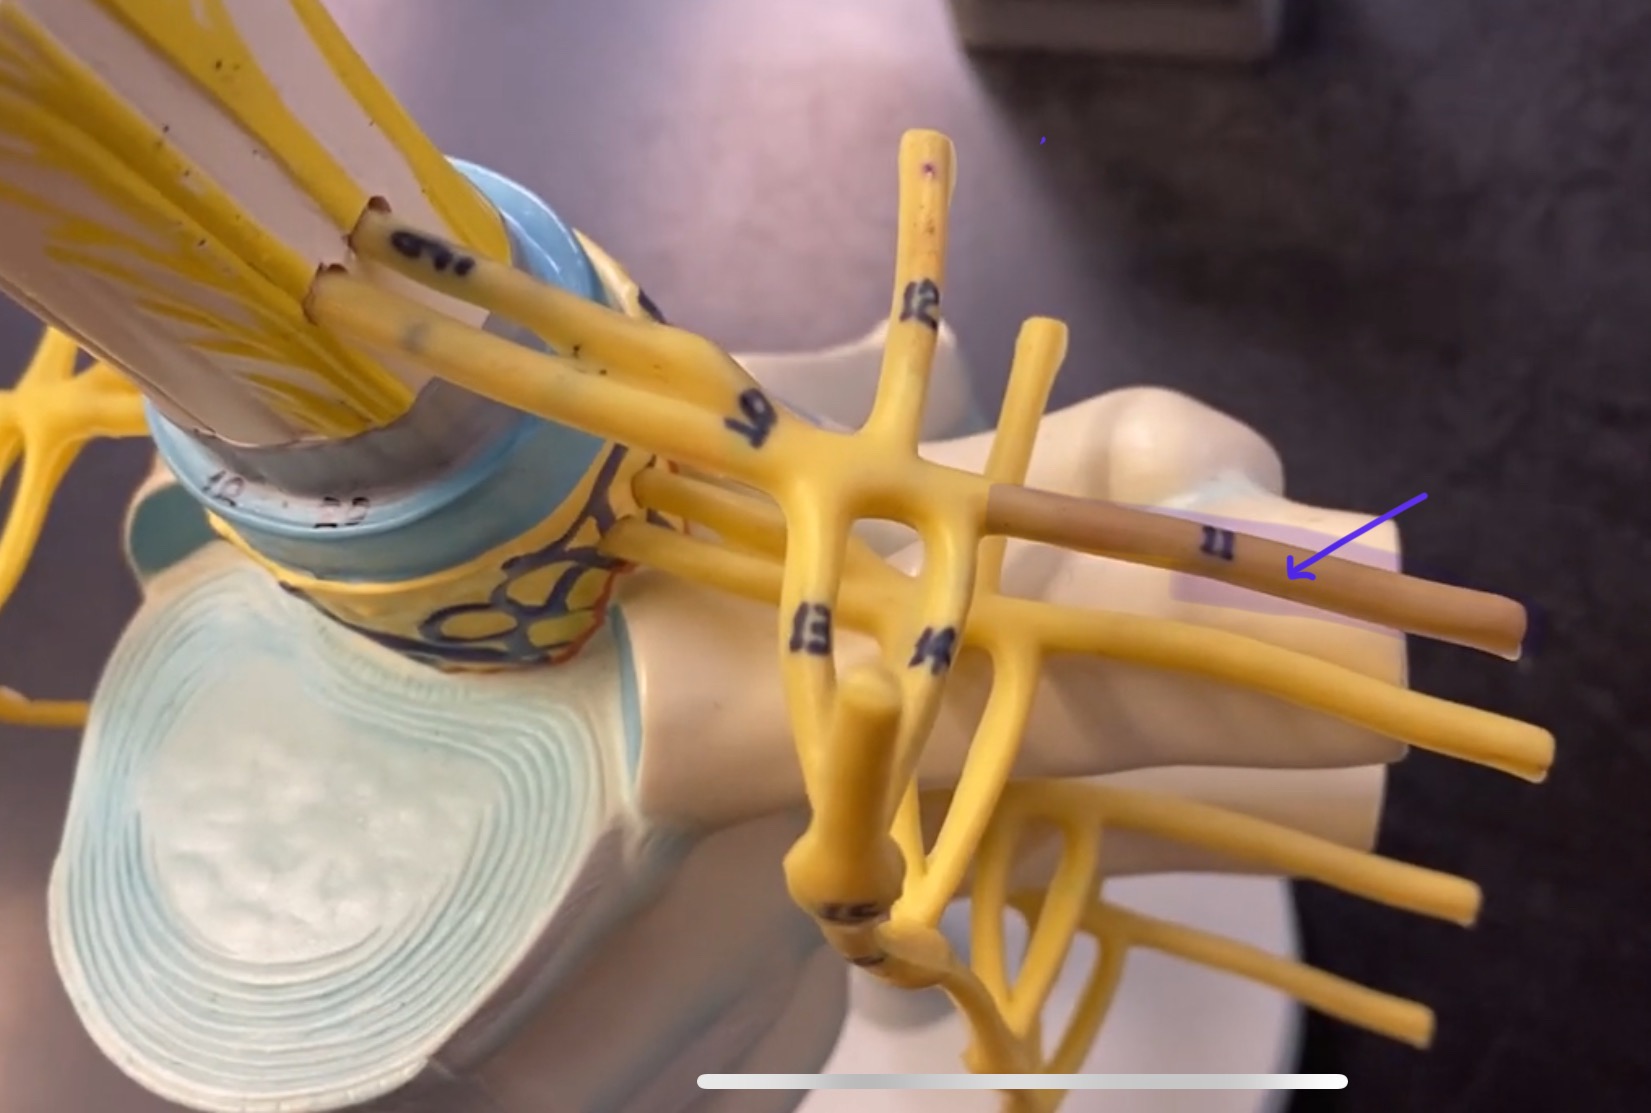

posterior (dorsal) root ganglion

What is the bulb here?

posterior (dorsal) root ganglion

posterior (dorsal) root

posterior (dorsal) root

anterior (ventral) root

anterior (ventral) root

dorsal ramus

dorsal ramus

ventral ramus

ventral ramus

rami communicantes

rami communicantes

sympathetic chain ganglia

sympathetic chain ganglia